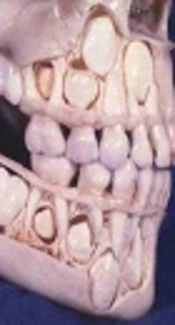

Dental Age Estimation in Southern Turkish Children: Comparison of Demirjian and Willems Methods

Halenur Altan,

Ahmet Altan*,

Ozlem Akinci Sozer